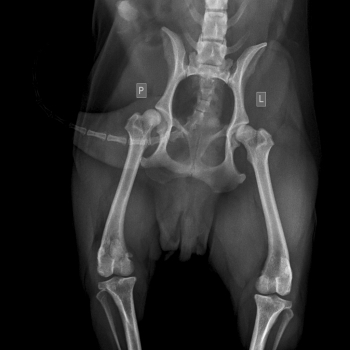

Badaniem można stwierdzić bolesność podczas biernych ruchów w stawie, mniejszy zakres ruchu w stawie, fenomen Ortolaniego – charakterystyczne „klikniecie” w stawie biodrowym wynikające z jego niestabilności. Najdokładniejszym badaniem jest badanie radiologiczne stawów biodrowych. Zdjęcie wykonuję się w projekcji grzbietowo-brzusznej – V-D, pies leży na grzbiecie (niekiedy konieczne jest wykonanie dodatkowych zdjęć w innych projekcjach). W większości przypadków do wykonania takiego zdjęcia konieczne jest uspokojenie pacjenta – sedacja i rozluźnienie mięśni – miorelaksacja, co uzyskuję się za pomocą iniekcyjnych środków farmakologicznych.

Objawy radiologiczne są różne w zależności od stopnia nasilenia zmian w stawie, dotyczyć mogą panewki stawu biodrowego, główki kości udowej lub obu struktur jednocześnie.